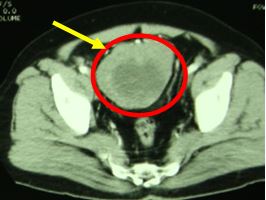

+ Siêu âm ổ bụng:

Vùng hạ vị có khối hỗn hợp âm kích thước 12 x 6,3cm.

Kết luận siêu âm: Nang thận trái, khối u vùng hạ vị theo dõi u mạc treo

Hình 1. Hình ảnh siêu âm ổ bụng: Khối u vùng hạ vị có hoại tử bên trong